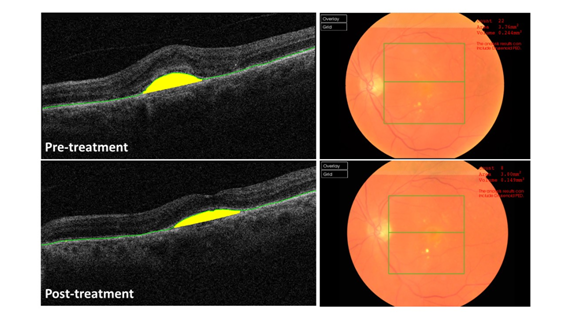

The validation of anti–VEGF therapy for nAMD created the need for non–invasive imaging modalities to monitor patient responses to treatment. Previous studies showed the usefulness of OCT automated segmentation software for monitoring retinal disease in response to therapy.13–15 Using OCT, clinicians are able to individualize injection frequencies according to individual patient’s visual needs. Although useful, the automated built in segmentation algorithms are known to have errors. Initial OCT segmentation software had a high error rate, partly due to the image–processing techniques and how to handle pathology, thus limiting its diagnostic utility.16–18 However, Spectral Domain–OCT (SD–OCT) systems integrated newer technology and improved segmentation software, allowing for improved image–analysis, including subretinal hyper reflective material (SHRM), and evaluation of pathology.19–22 In addition to segmentation software, SD–OCT systems are integrated with analysis software designed to automatically detect deviations from the RPE contour and quantify their surface area and volume.23–29 Assuming classic CNV lesions form half–ellipsoid shapes; one can use such tools with automatic segmentation software in serial imaging to monitor nAMD disease progression and response to therapy (Figure 2).30–32

Figure 2 OCT software identification of CNV lesions showing automatic delineation of the RPE and accompanying fundal view A) Pre-treatment and B) Post-treatment.